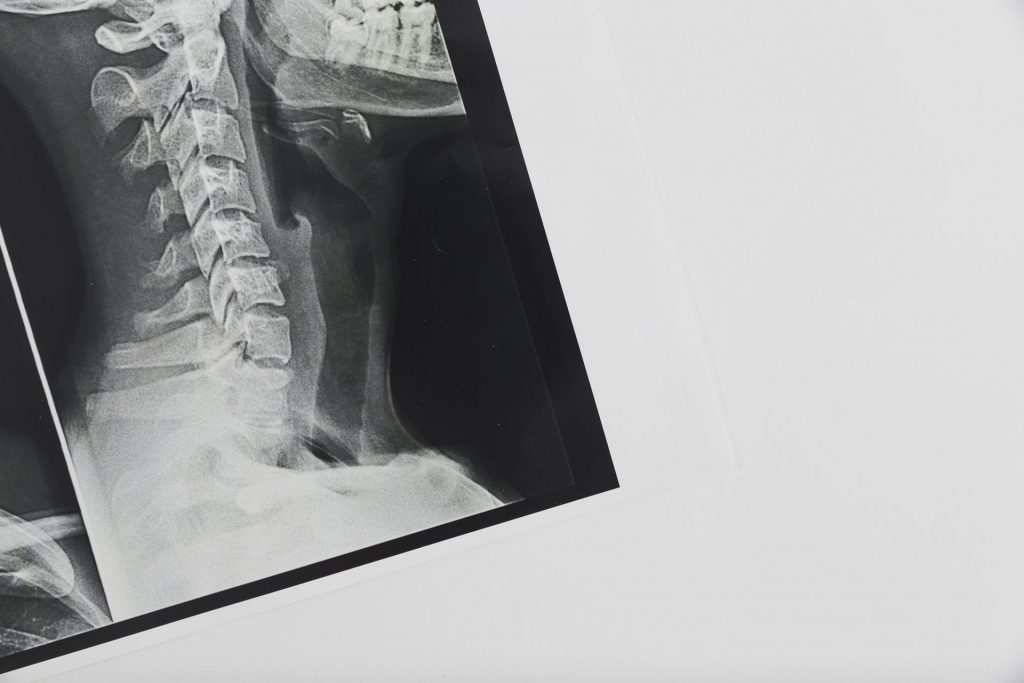

Il caso in questione riguarda un incidente stradale in cui l’automobilista ha subito un colpo di frusta, una lesione spesso associata a incidenti automobilistici. La problematica centrale si concentra sul rifiuto della compagnia assicurativa di risarcire il danno senza una prova radiografica. La sentenza emessa dal giudice di pace di Venezia con il numero 769/2016 ha stabilito un precedente importante in questa materia.

Il caso specifico trattato dal giudice di pace di Venezia riguardava un paziente che aveva subito un colpo di frusta, una lesione che raramente mostra evidenze visibili tramite radiografia. Nonostante ciò, il medico aveva riscontrato un danno biologico permanente stimato tra il 2 e il 3 percento. Di conseguenza, la compagnia assicuratrice, oltre a essere stata segnalata all’Ivass (l’Istituto per la vigilanza sulle assicurazioni), è stata condannata a risarcire il cliente per i danni subiti e per le spese legali sostenute. Questo caso sottolinea l’importanza di una valutazione medica accurata e indipendente nella determinazione dei risarcimenti assicurativi, soprattutto in situazioni in cui i danni fisici potrebbero non essere immediatamente evidenti attraverso metodi diagnostici convenzionali.